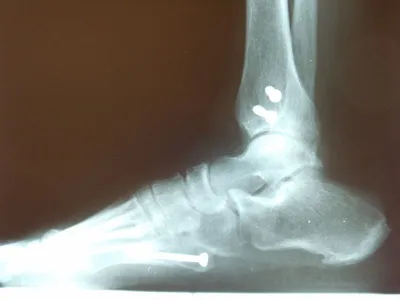

The same fracture is seen 8 weeks later with bridging across the fracture and fracture callus